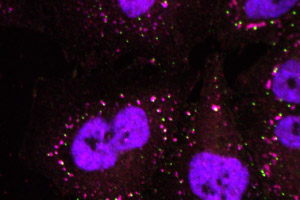

L’équipe de Christine Vande Velde, chercheuse au Centre de recherche du centre hospitalier de l’Université de Montréal (CRCHUM), dévoile le rôle majeur des granules de stress dans le développement de […]